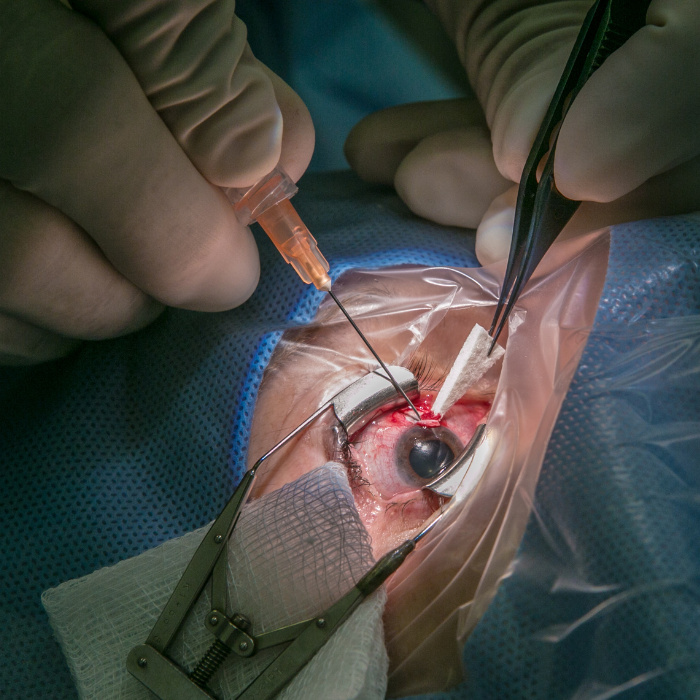

1. Trabeculectomia

È la chirurgia tradizionale del glaucoma e rimane una delle più efficaci.

Consiste nel creare un piccolo canale di drenaggio che permette all’umore acqueo di defluire verso una zona di riassorbimento sotto la congiuntiva (bleb filtrante).

👉 Obiettivo: ridurre in modo stabile la pressione oculare.

👉 Durata: circa 30–40 minuti, in anestesia locale.

👉 Recupero: graduale, con controlli frequenti nelle prime settimane.